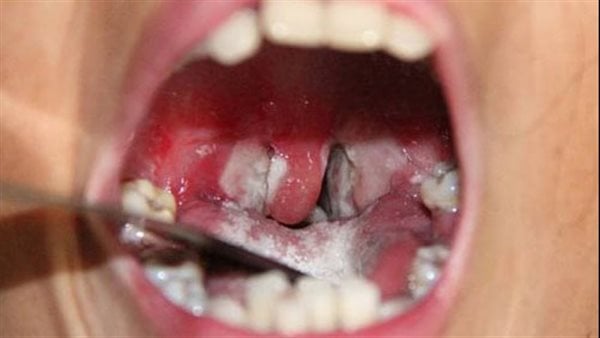

أفادت مصادر محلية في بلدية تناها التابعة لمقاطعة كنكوصه بولاية لعصابة، بوفاة سبعة أشخاص وإصابة أكثر من 70 آخرين بمرض يُرجّح أنه الدفتيريا.